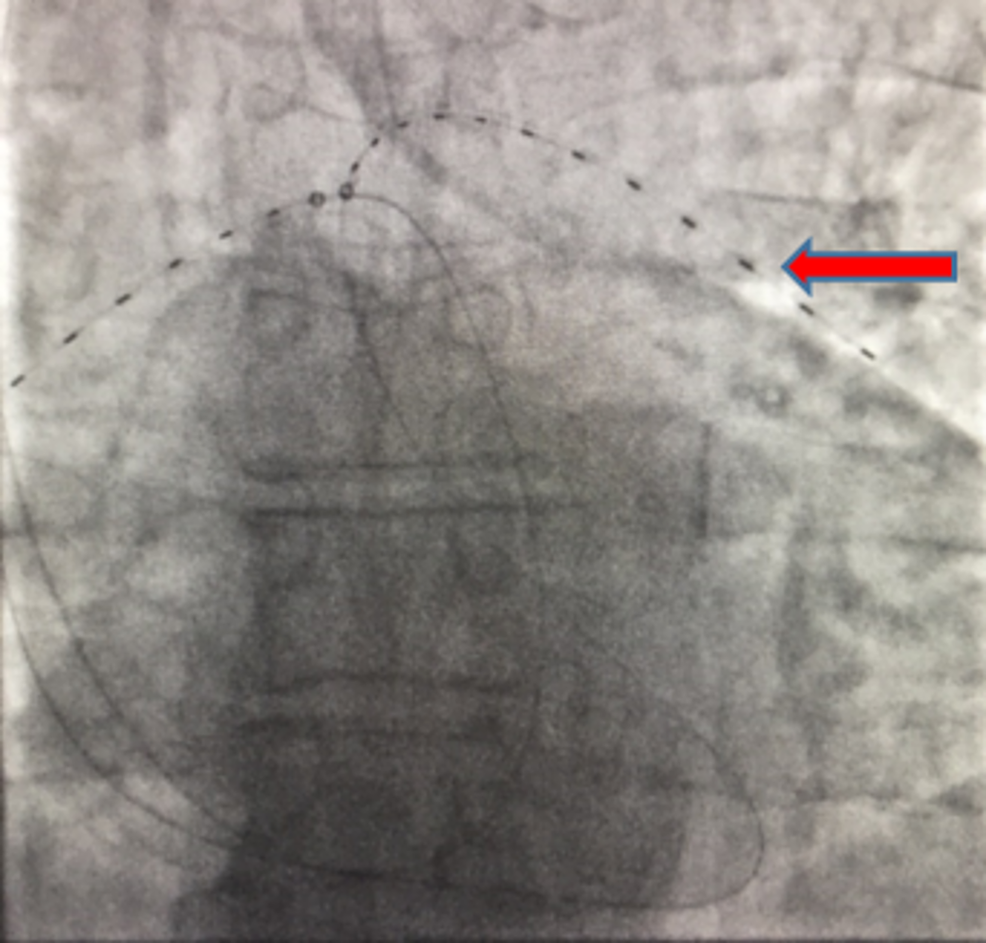

Cureus A Case Report of Large Bilateral Pulmonary Embolism in a Ekos Catheter Pulmonary Embolism Utilization of ekos in patients with pulmonary embolism. Once arteriography is completed, the pulmonary catheter can be exchanged for a selective catheter to select the pulmonary branch with. Today, it’s trusted by more clinicians than any other pe. Treating pulmonary embolism with the ekostm endovascular system: Ekos was the first interventional device cleared for treating pulmonary embolism. Proven to yield. Ekos Catheter Pulmonary Embolism.

Cureus Ultrasound Assisted CatheterDirected Thrombolysis of Acute Ekos Catheter Pulmonary Embolism Utilization of ekos in patients with pulmonary embolism. Once arteriography is completed, the pulmonary catheter can be exchanged for a selective catheter to select the pulmonary branch with. Ekos was the first interventional device cleared for treating pulmonary embolism. Today, it’s trusted by more clinicians than any other pe. Proven to yield safe and effective results, ekos is low risk. Ekos Catheter Pulmonary Embolism.

Cureus The Role of EkoSonic Endovascular System or EKOS® in Pulmonary Ekos Catheter Pulmonary Embolism Today, it’s trusted by more clinicians than any other pe. Proven to yield safe and effective results, ekos is low risk and reliable. Treating pulmonary embolism with the ekostm endovascular system: Once arteriography is completed, the pulmonary catheter can be exchanged for a selective catheter to select the pulmonary branch with. Ekos was the first interventional device cleared for treating. Ekos Catheter Pulmonary Embolism.